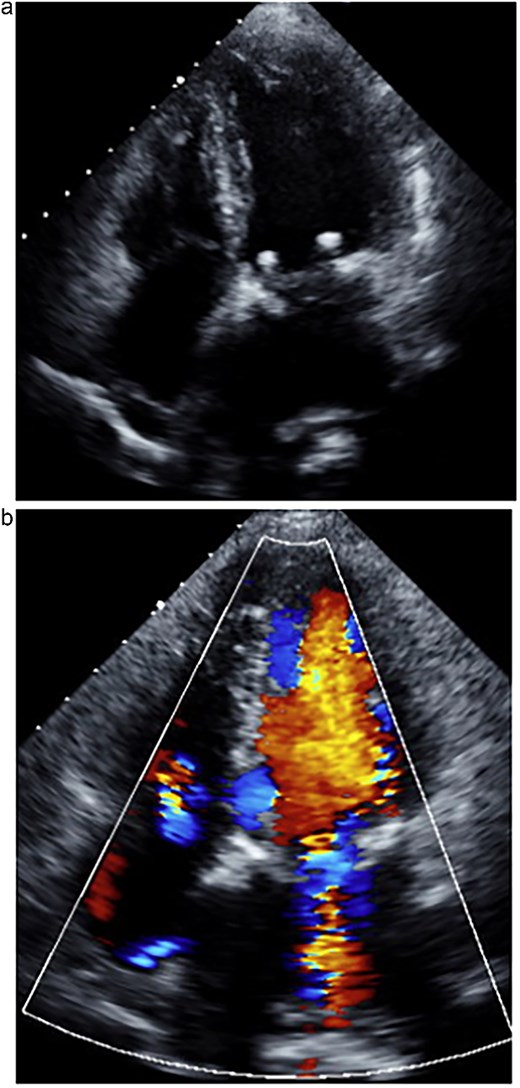

The patient was extubated on postoperative day (POD) 1 and discharged home on POD 13. Postoperative TTE showed no residual MR, a LVEF of 43%, and reduced left atrial volume (Fig. 3). At 1-year follow-up, the patient remained asymptomatic with stable valve function and no recurrence of MR.

One week postoperative transthoracic echocardiography. (a) The left atrium was reduced in size. (b) Mitral regurgitation was well controlled.